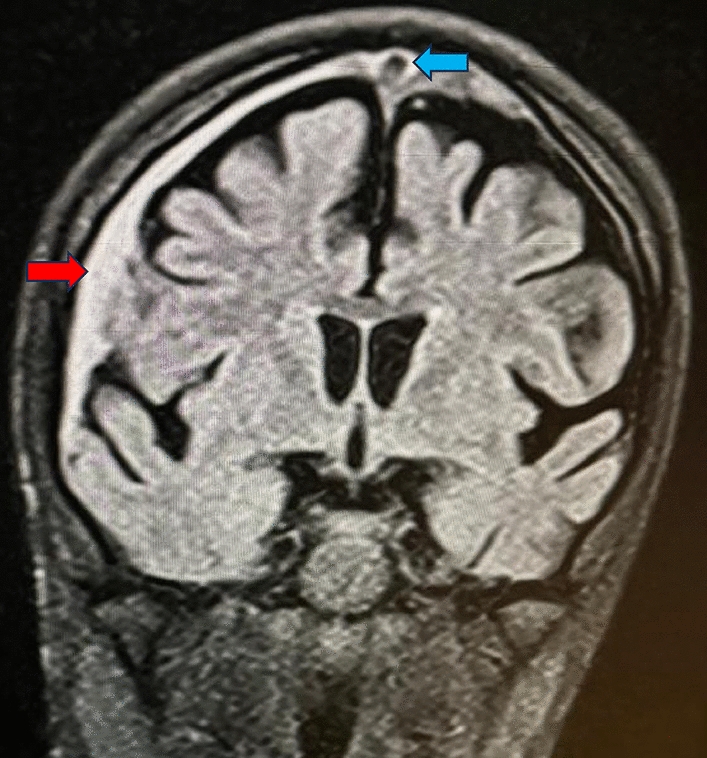

Endometriosis is a benign gynaecological condition causing chronic pelvic pain, impaired fertility and dysmenorrhoea. It is difficult to describe the lesion distribution due to the complexity of the disease, inconsistent pattern and sometimes even absent progression.

Mean age of the patients was 32.25 ± 6.107 years, and mean BMI was 23.9 ± 3.36 kg/m2. 47.2% had taken medical treatment for a period of 5.9 ± 11.7 months. Regarding parity, 75.4% were nulliparous, and 40.8% patients had infertility as co-existing complaint. According to #ENZIAN, the left ovarian involvement was observed in 67.4% and bilateral involvement noted in 46.1%. A (rectovaginal vagina and septum) was involved in 61% cases, B (uterosacral ligaments and pelvic wall) 63.58% on left and 60.33% on right and C (rectum and sigmoid colon) 33.1% cases.